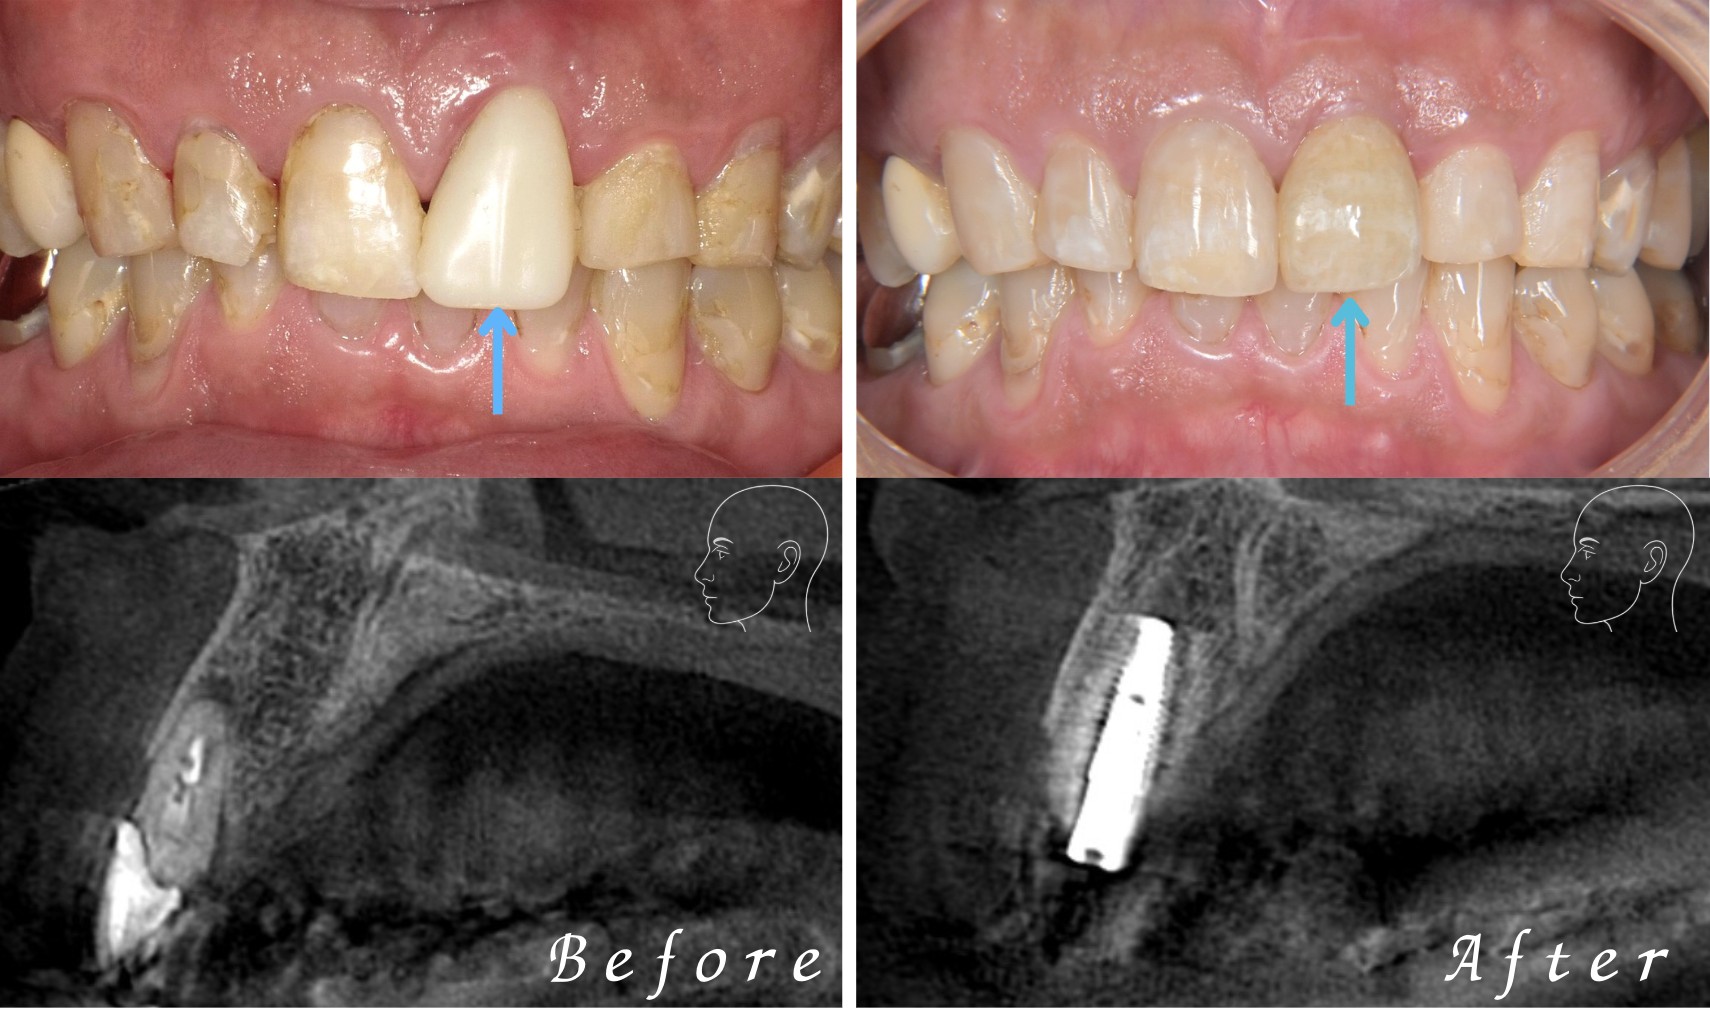

前歯の審美不良を抜歯即時インプラントで改善